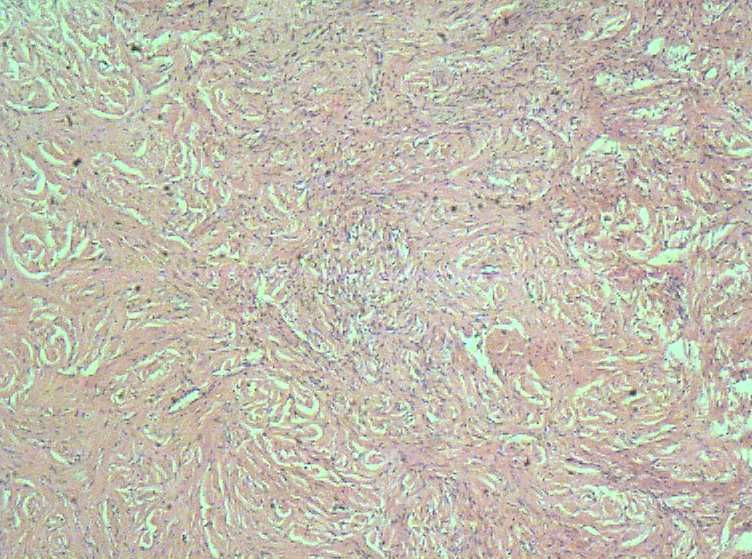

29 左侧卵巢肿瘤大小8*6*6质硬、输卵管外观正常。右附件外观正常

肉眼检查:(腹腔镜术)苍白色圆柱状物一堆约10*10*4CM质硬,未见囊肿及出血和坏死。取一

B超医生考虑:勃伦纳瘤 ?

本人考虑纤维瘤 ,请各位老师点评下。

良性梭形细胞肿瘤,待做特殊染色定纤维瘤或卵泡膜细胞瘤。

就这几张图而言,支持纤维瘤。你再找找看胞浆里面有没有脂质空泡,与卵泡膜细胞瘤鉴别。

胞浆里面有没有脂质空泡,也没有看到上皮样细胞  都是些纤维组织

送检组织均匀一致,没有见到什么特别的地方  苍平质硬 (韧)没有粘液及小囊 未见出血、坏死

就这几张图的质量而言,不是太清楚,勉强给个纤维瘤的考虑,多取材与卵泡膜细胞瘤鉴别。